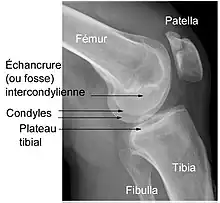

Éléments d'anatomie du genou

(vue inférieure fémur droit)

Le genou naturel est composé de trois parties osseuses :

- l’extrémité inférieure du fémur qui a la forme de deux roues accolées : les condyles ;

- l’extrémité supérieure du tibia, encore appelé plateau tibial ;

- la patella (ou rotule) : petit bouclier situé sur l’avant du fémur.